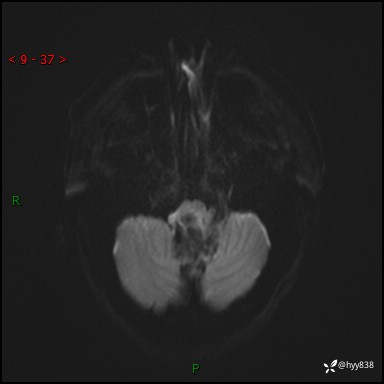

性别:女

年龄:47岁

简要病史:头晕1年余,间断恶心不伴呕吐

颅脑MRI平扫+DWI

轴内、轴外占位

轴内或轴外肿瘤